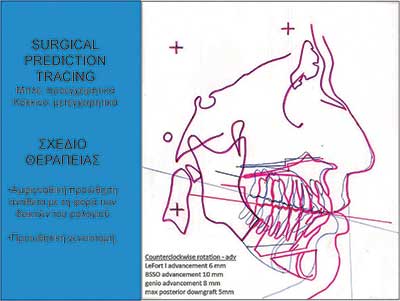

Οι εικόνες 4, 5 και 6 δείχνουν παραδείγµατα ασθενών που υποβλήθηκαν σε αµφιγναθική προώθηση. Στην εικόνα 4 πρόκειται για σύγκριση προεγχειρητικής µε 2 µήνες µετεγχειρητική πλάγια κεφαλοµετρική ακτινογραφία, όπου διακρίνεται η χοανοειδής διεύρυνση του φαρυγγικού αυλού στο οπισθοϋπερώιο και στο οπισθογλώσσιο τµήµα του. Ο συγκεκριµένος ασθενής βελτίωσε τον ∆ΑΥ από τα 100 επεισόδια / ώρα προεγχειρητικά στα 7 επεισόδια / ώρα µετεγχειρητικά, έτσι ώστε να µη χρειάζεται πλέον να κοιµάται µε τη ρινική µάσκα CPAP. Στην εικόνα 5α βλέπουµε µέση οβελιαία τοµή από υπολογιστική τοµογραφία του αεραγωγού ασθενούς µε προεγχειρητικό ∆ΑΥ 55 επεισόδια / ώρα και ελάχιστο καταγεγραµµένο κορεσµό αιµοσφαιρίνης 77%. ∆ιακρίνεται πλήρης οπισθοϋπερώια απόφραξη και πολύ σοβαρή οπισθογλώσσια στένωση. Στηνεικόνα 5β διακρίνεται ο σχεδιασµός της αµφιγναθικής προώθησης και της συµπληρωµατικής οριζόντιας γενειοτοµής στον ίδιο ασθενή. Στην εικόνα 5γπαρατίθεται η σύγκριση του εµβαδού διατοµής του φαρυγγικού αυλού αυτού του ασθενούς οπισθοϋπερώια και οπισθογλώσσια πριν και 1 έτος µετά την επέµβαση. Είναι εµφανέστατη η αύξηση των διαστάσεων του αεραγωγού. Οι εικόνες 6α και 6β αποτελούν πλάγιες και κατά µέτωπο τρισδιάστατες απεικονίσεις αεραγωγού ασθενούς πάσχοντος από βαρύτατο ΣΑΑΥ προ και µετά την αµφιγναθική προώθηση.

Εικόνα 5β